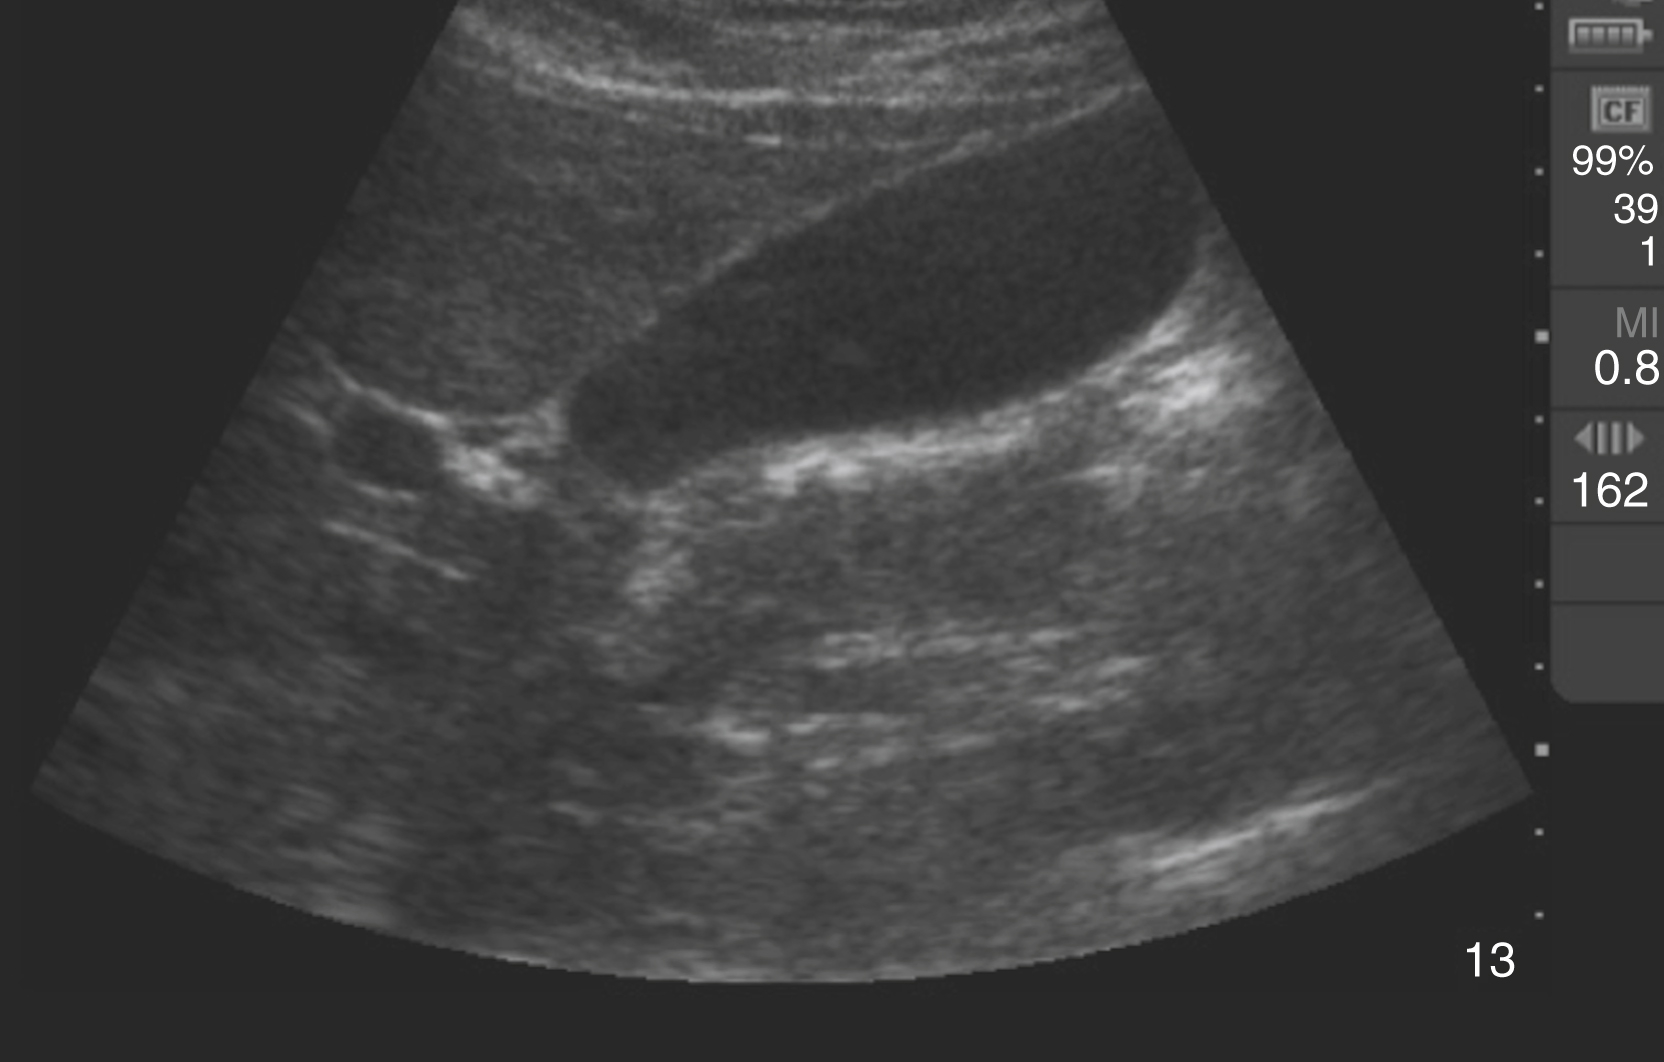

Pathology

Hydronephrosis is characterized by dilation and anechoic fluid accumulation within the renal pelvis and calyces, ranging from mild to severe ( Fig. e3.6 ). Renal and/or ureteral calculi may be identified as echogenic foci with associated shadowing and are usually located within the kidney (nonobstructive) or in the renal pelvis, proximal ureter, or uretero-vesicular junction. Color Doppler placed over the kidney can help differentiate mild hydronephrosis from the renal vasculature, as well as possibly accentuate any renal stones by producing the renal twinkle artifact.

Hydronephrosis with dilation of the calyces and renal pelvis of the kidney showing thinning of the cortex, signifying severe hydronephrosis.